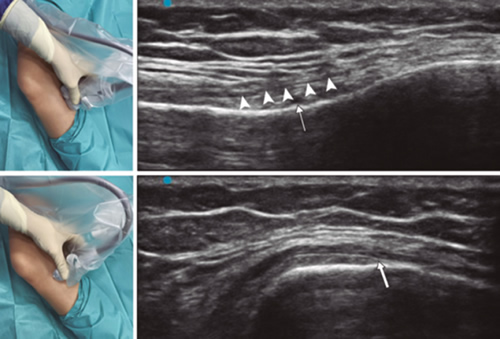

Figura 1

Figura 2

Figura 3

Figura 4

Figura 5